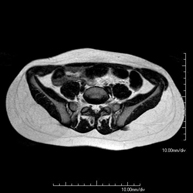

Prova diagnòstica no invasiva que consisteix en l'obtenció d'imatges d'alta definició anatòmica de la pelvis mitjançant l'ús d'un camp electromagnètic i ones de ràdio (amb un emissor i un receptor). No utilitza radiació ionitzant. Es realitza per a l'estudi de patologies d'úter, d'ovari, de trompes i de vagina, ja siguin d'origen tumoral, inflamatori o vascular. També permet valorar les estructures adjacents localitzades a la pelvis i la identificació de les seves alteracions. De vegades és necessari l'ús de contrast intravenós (Gadolini) per caracteritzar les lesions. - RM Pelvis masculina

Prova diagnòstica no invasiva que consisteix en l'obtenció d'imatges d'alta definició anatòmica de la pelvis masculina mitjançant l'ús d'un camp electromagnètic i ones de ràdio (amb un emissor i un receptor). No utilitza radiació ionitzant. No requereix preparació prèvia. En algunes ocasions necessita l'ús de contrast paramagnètic (Gadolini) per caracteritzar les lesions. Aquesta prova permet valorar òrgans com la bufeta urinària, la unió entre els urèters i la bufeta, la pròstata, les vesícules seminals, la uretra i els ossos de la pelvis, entre d'altres. - RM de Fetge